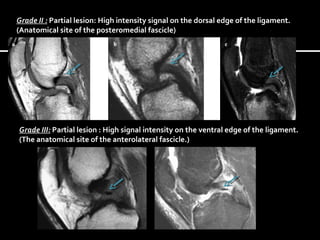

MRI classification was first published by Gross et al.

Grade I : Intraligamentous lesion : High signal intensity within the ligament.

Grade II : Partial lesion: High intensity signal on the dorsal edge of the ligament.

(Anatomical site of the posteromedial fascicle)

Grade III: Partial lesion : High signal intensity on the ventral edge of the ligament.

(The anatomical site of the anterolateral fascicle.)